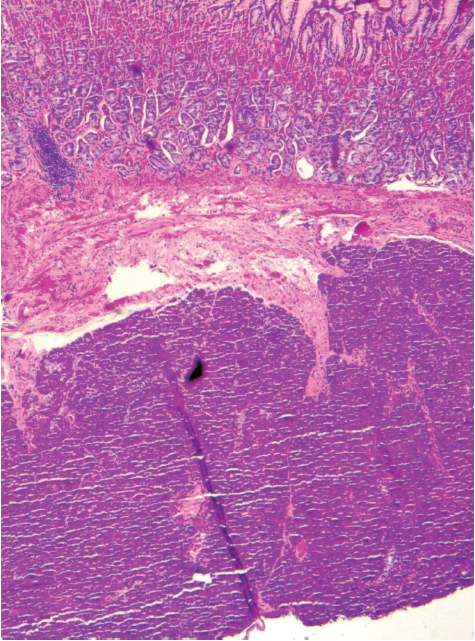

病理提示,胃固有肌层内可见腺体分叶状分布,无异型,考虑为胰腺组织,以胰腺腺泡为主,可见胰岛细胞(图5和图6)。

图5 病理(×40):胃固有肌层内可见腺体分叶状分布,无异型,考虑为胰腺组织,以胰腺腺泡为主

图6 病理(×200):胰腺组织中可见胰岛细胞(黑色箭头)